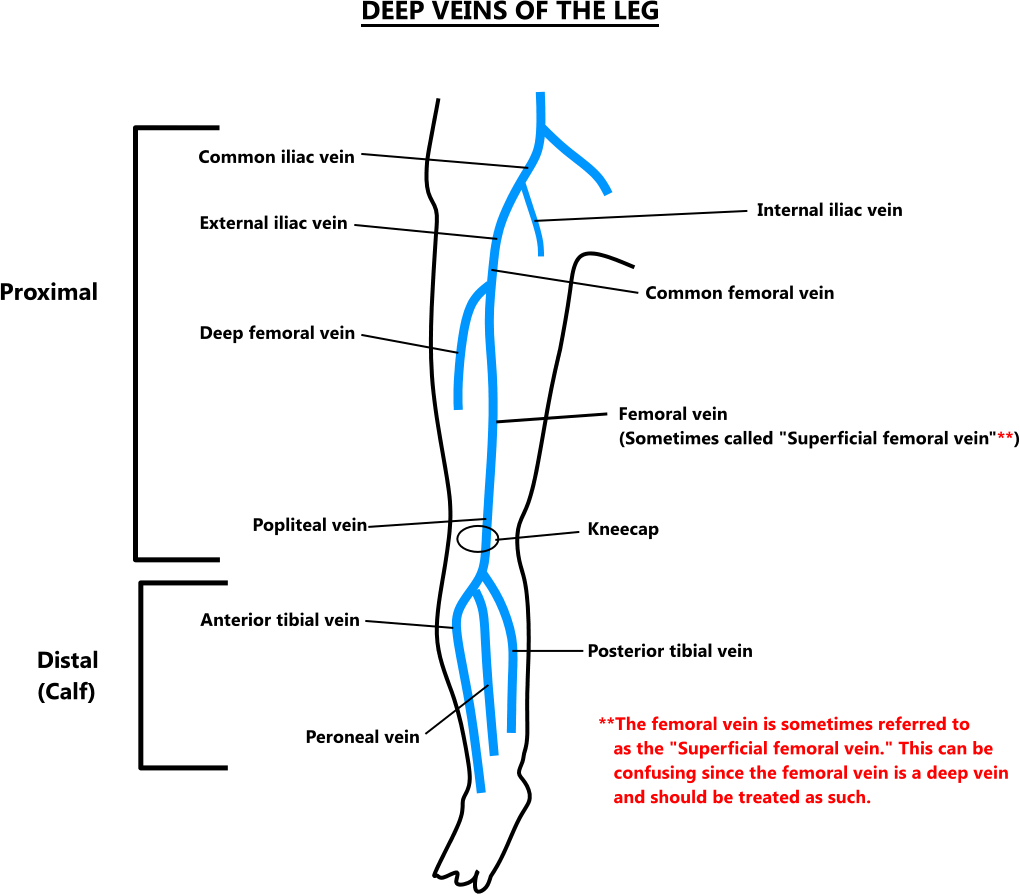

deep vein veins thrombosis leg

vte distal proximal dvt veins calf

venous dvt deep thrombosis lower extremity system evlt